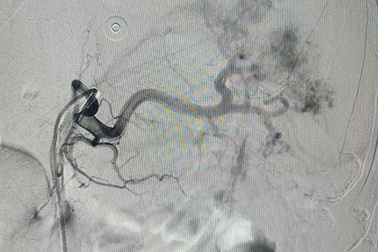

Nút động mạch cứu bệnh nhân vỡ lách máu tràn ổ bụngNhập viện trong tình trạng mất máu cấp sau tai nạn giao thông, nam bệnh nhân được bác sĩ xác định bị vỡ lách. Các bác sĩ đã thực hiện phương pháp nút động mạch cầm máu giúp bệnh nhân qua nguy kịch.